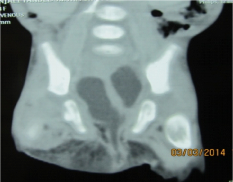

Investigations revealed anaemia, leucocytosis, deranged electrolytes and metabolic acidosis. USG was suggestive of a suspicious obturator hernia on right side. CT scan was suggestive of bulging of a large complex cystic structure with air-fluid level on the right side. Sagittal reformations also suggested the inferior descent of the cystic structure through the perineal floor (Figures 4 &5). The deranged laboratory parameters were corrected and the child was taken for emergency exploration. Intra-operatively, it was found that the massive hydrocolpos was protruding through the perineum as the bulge. There was no perineal or obturator defect. Drainage of the massive hydrocolpos was done by an abdominal vaginostomy (Figures 6&7).

Figure 4 Axial scan at the level of perineum s/o bulging of the fluid filled structure on the right side.